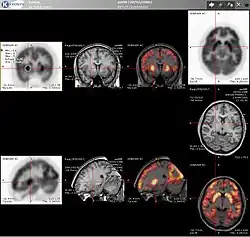

Combination of PET with CT or MRI

PET scans are increasingly read alongside CT or MRI scans, with the combination (co-registration) giving both anatomic and metabolic information (i.e., what the structure is, and what it is doing biochemically). Because PET imaging is most useful in combination with anatomical imaging, such as CT, modern PET scanners are now available with integrated high-end multi-detector-row CT scanners (PET–CT). Because the two scans can be performed in immediate sequence during the same session, with the patient not changing position between the two types of scans, the two sets of images are more precisely registered, so that areas of abnormality on the PET imaging can be more perfectly correlated with anatomy on the CT images. This is very useful in showing detailed views of moving organs or structures with higher anatomical variation, which is more common outside the brain.

At the Jülich Institute of Neurosciences and Biophysics, the world's largest PET–MRI device began operation in April 2009. A 9.4-tesla magnetic resonance tomograph (MRT) combined with a PET. Presently, only the head and brain can be imaged at these high magnetic field strengths.[73]

For brain imaging, registration of CT, MRI and PET scans may be accomplished without the need for an integrated PET–CT or PET–MRI scanner by using a device known as the N-localizer.[31][74][75][76]